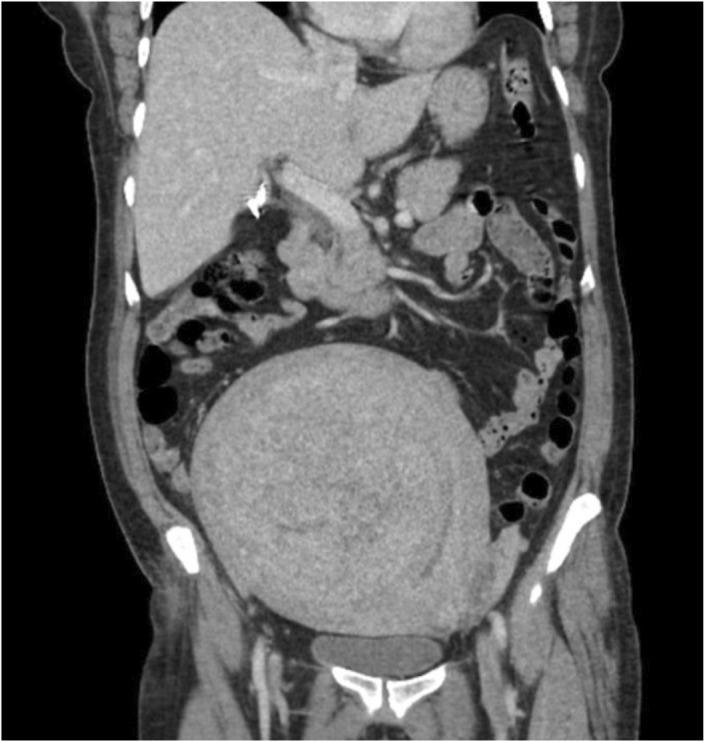

We highlight a novel case of TAFRO syndrome with disseminated intravascular coagulation, neurologic changes, and non-ischemic cardiomyopathy. Through this clinical vignette, we hope to raise awareness of TAFRO syndrome and encourage providers to maintain a high level of suspicion for it when evaluating patients who meet the diagnostic criteria.

我们重点介绍了一例伴有弥散性血管内凝血、神经学改变和非缺血性心肌病的TAFRO综合征新病例。通过这个临床案例,我们希望提高对TAFRO综合征的认识,并鼓励医疗人员在评估符合诊断标准的患者时,对该综合征保持高度怀疑。